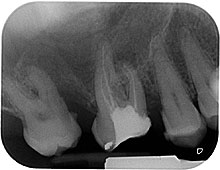

• Dies erfolgt röntgenologisch mit einer sogenannten Nadelaufnahme

• Nun erfolgt in mehreren Arbeitsschritten, oft auch mehreren Sitzungen, die Aufbereitung, Reinigung, Erweiterung, Spülung, Desinfektion, das Versorgen mit Medikamenten sowie die Füllung des Wurzelkanals. Diese Behandlung wird von mehreren röntgenologischen Kontrollaufnahmen begleitet Siehe Röntgenbild: